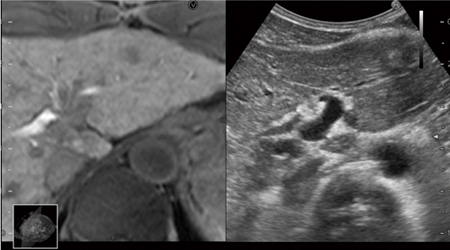

EOB-MRIを用いたRVS画像

Bモードでは不明瞭な胆管の走行が把握可能となる。